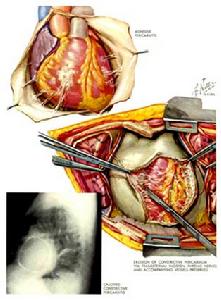

心臟手術剖析圖具體操作:

3、解除心包填塞:大量滲液或有心包填塞症狀者,可施行心包穿刺術抽搐液減壓。

4、主要決定於病因:如並發於急性心肌梗塞、惡性腫瘤或系統性紅斑狼瘡等,則預後嚴重。如為結核性或化膿性心包炎等,及時有效的治療,包括必要的心包穿刺抽液或心包切開排膿,可望獲得痊癒。部分可遺留心肌損害和發展成縮窄性心包炎。